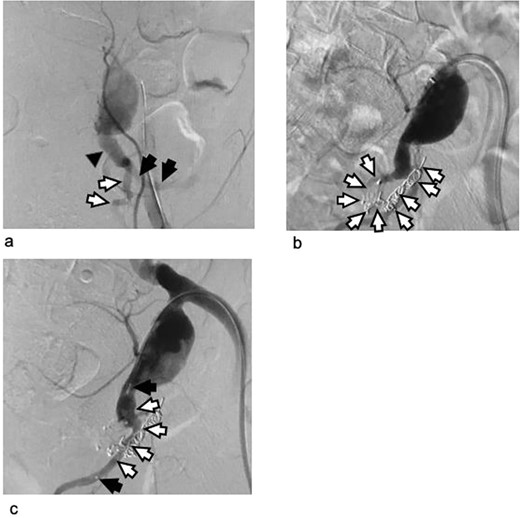

Two weeks later, we performed open surgery as the second stage of the hybrid procedure. We exposed the internal iliac artery through a median lower abdominal incision and transperitoneal approach. The neck of the internal iliac artery aneurysm was too short for clamping or ligation. We decided to clamp the common and external iliac artery instead to achieve proximal control. We then opened the aneurysm without having to take surgical control of the distal branches. There was no bleeding from the aneurysm. We closed the origin of the distal internal iliac artery with a 4–0 pledgeted suture. The shortness of the neck of the aneurysm and the calcification extending from the common into the external iliac artery did not allow us to ligate or directly close the origin of the artery. We therefore interposed a 7-mm Dacron artificial graft (J graft, Japan Lifeline Co., Ltd., Tokyo, Japan) between the common and external iliac artery for proximal repair (Figure 3).

Intraoperative findings during the open procedure as the second stage of hybrid intervention. (a) Dissection of the vessels proximal to the internal iliac artery aneurysm: We clamped the common iliac artery and external iliac artery for proximal control. The neck of the internal iliac artery aneurysm was very short (arrow). (b) Without surgical clamping of the distal branches, we opened the aneurysm. The origin of the distal internal iliac artery and the tip of the vascular plug obstructing it are visible. No bleeding into the internal iliac artery aneurysm can be seen. The first-stage embolization had completely controlled the distal blood flow. Arrow: the tip of the vascular plug. Circle: the orifice of the internal iliac artery distal to the aneurysm. (c) We ligated the origin of the distal internal iliac artery with a 4–0 pledgeted suture to avoid dislodgement of the vascular plug and delayed bleeding. Arrow: one of the two pledgets used in the ligation. (d) The common iliac artery could not be directly closed. We interposed the artery for proximal repair. The aneurysm wall was resected as much as possible.

CIA: common iliac artery, EIA: external iliac artery, IIAA: internal iliac artery aneurysm, UT: ureter.

We resected the free wall of the aneurysm as much as possible and sutured the margins. The duration of the operation was 2.25 hours, and the blood loss was 70 mL. A red blood cell transfusion was not required.